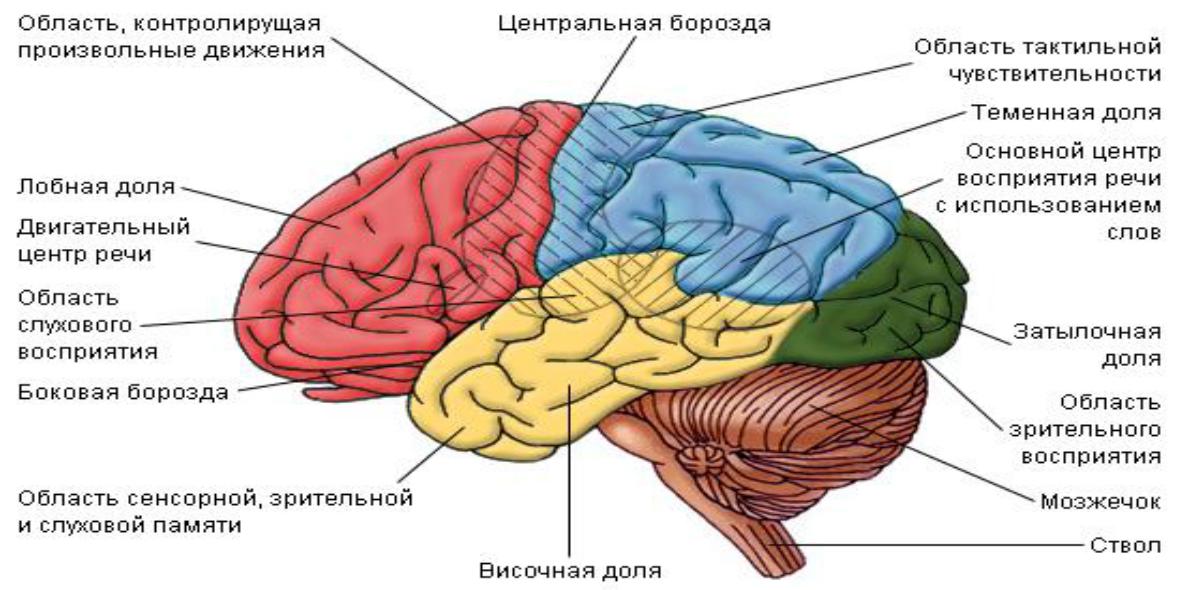

Схема чувствительных зон новой коры мозга